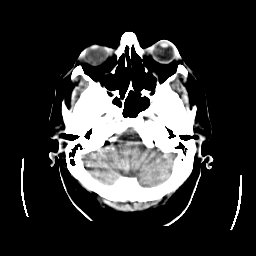

CT Study #2 -- Slice #5